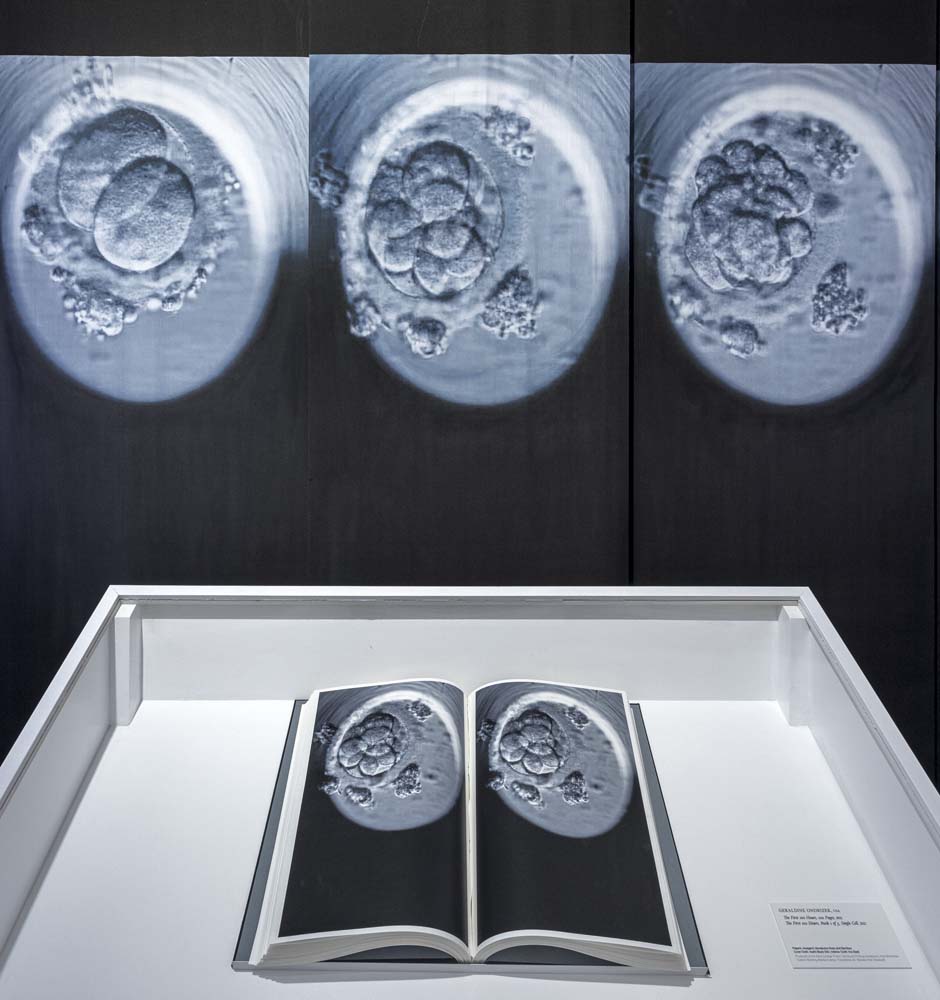

The First 100 Hours

The installation of books, silk panels and film, The First 100 Hours was made in collaboration with Dr. Shizuko Takahashi at the University of Tokyo, Department of Biomedical Ethics.

The work originated from in vitro fertilization films. Each still image captures the most significant stages in early egg development to see if they are viable to implant. The embryo in this film was a successful pregnancy. This is of course not always the case, invitro fertilization is a complex process. The work documents the most important moments when genetic and epigenetic factors form to create each unique being. Epigenetic changes are modifications to DNA that regulate whether genes are turned on or off. Epigenetic responses are both inherited and accumulated in our lifetime and thus affect our genetic markers. From the time of conception, our internal and external environment cause epigenetic changes.

Work in the Exhibition:

The First 100 Hours, 100 Pages, 2022

The First 100 Hours, Book 1 of 5, Single Cell, 2022

Artist books

Awagami, Murakumo Kozo and Bamboo paper

Asahi Black Silk, Iris Steel

Custom Binding, Marika Esarey

Translation, Dr. Shizuko Imai Takahash

Reed College Press

The First 100 Hours, Multiple Embryos in Gestation, 2022

Video, Music by Aden Qamar using recordings of plants.

Editing by Henry Sullivan

The First 100 Hours, Cleavage, 2 Cell Stage, 8 Cell Stage, 32 Cell Stage,

Blastocyst, 2022

Five Silk Panels, Haraboi Silk Panels Hand Painted, Digital Print